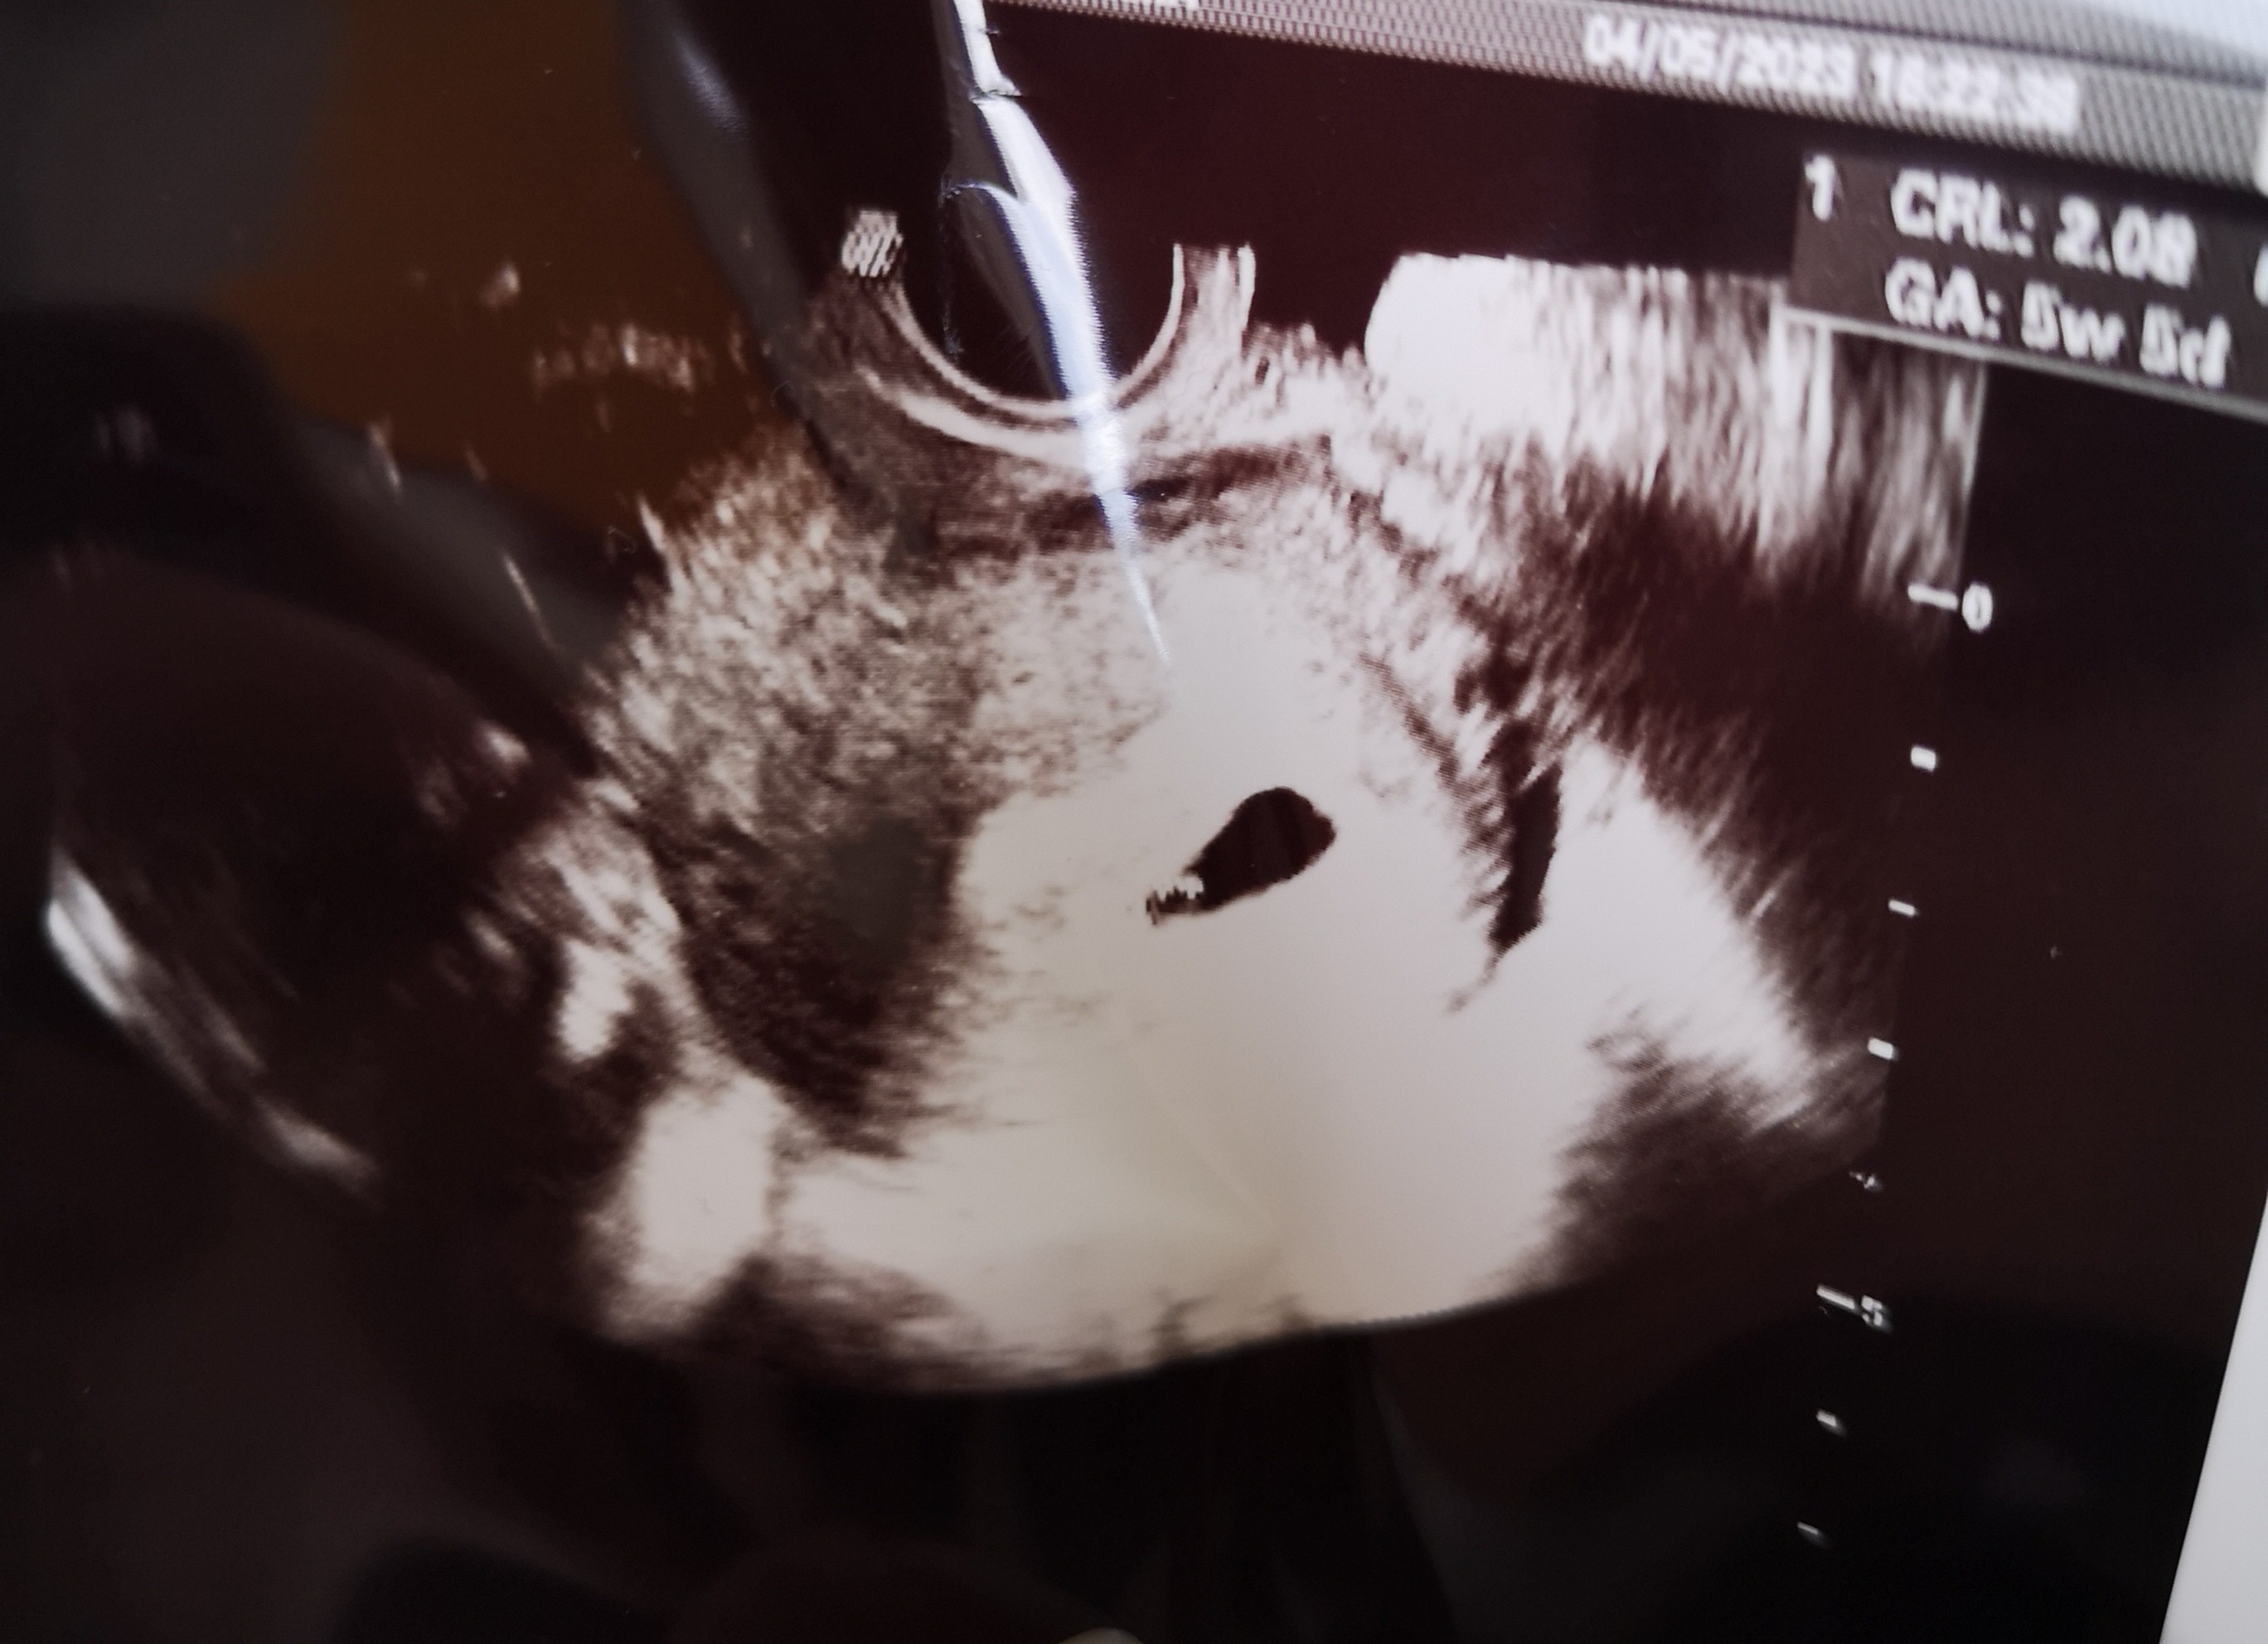

Dzień dobry, dzisiaj 04.05 byłam u ginekologa na USG to 5tydz i 5dni ciąży . Pani ginekolog powiedziała, że zarodek jest nisko ułożony i nic nie powiedziała, zapytałam się czy to coś poważnego odpowiedziała, że nie jest to nic poważnego bo macica się powiększa. Jak myślicie czy to może być coś poważnego?

Czy mam się martwić?

Poniżej zdjęcie

• IMG_20230504_180726.jpg